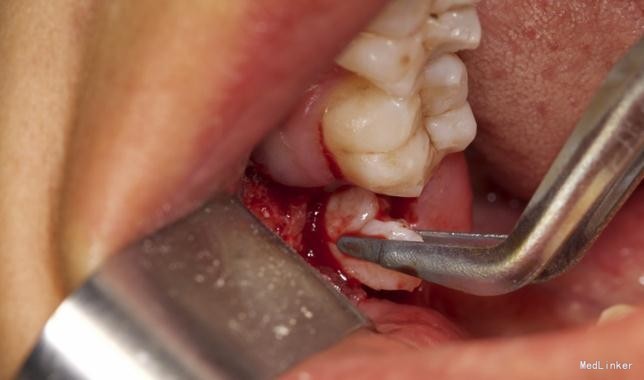

左下8水平阻生拔除

拔除术

效果很好,患者满意